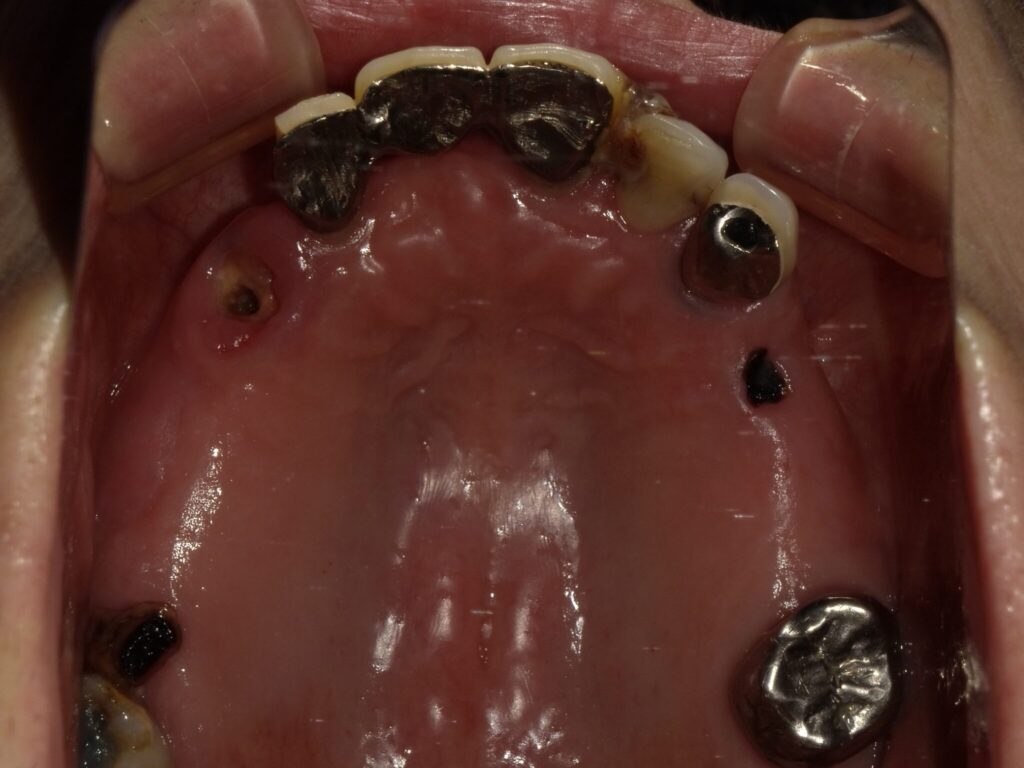

全顎治療症例

| 主訴 | 全体的に見た目を綺麗にしたい。奥歯でしっかり噛みたい。 |

| 診断名・ 主な症状 |

臼歯部欠損 |

| 年齢 | 70歳 |

| 治療内容 | インプラント埋入(右上4・6,左上4・6,右下6,左下6) ジルコニアBr(右上3―左上3) ジルコニア(右下5,左下5) |